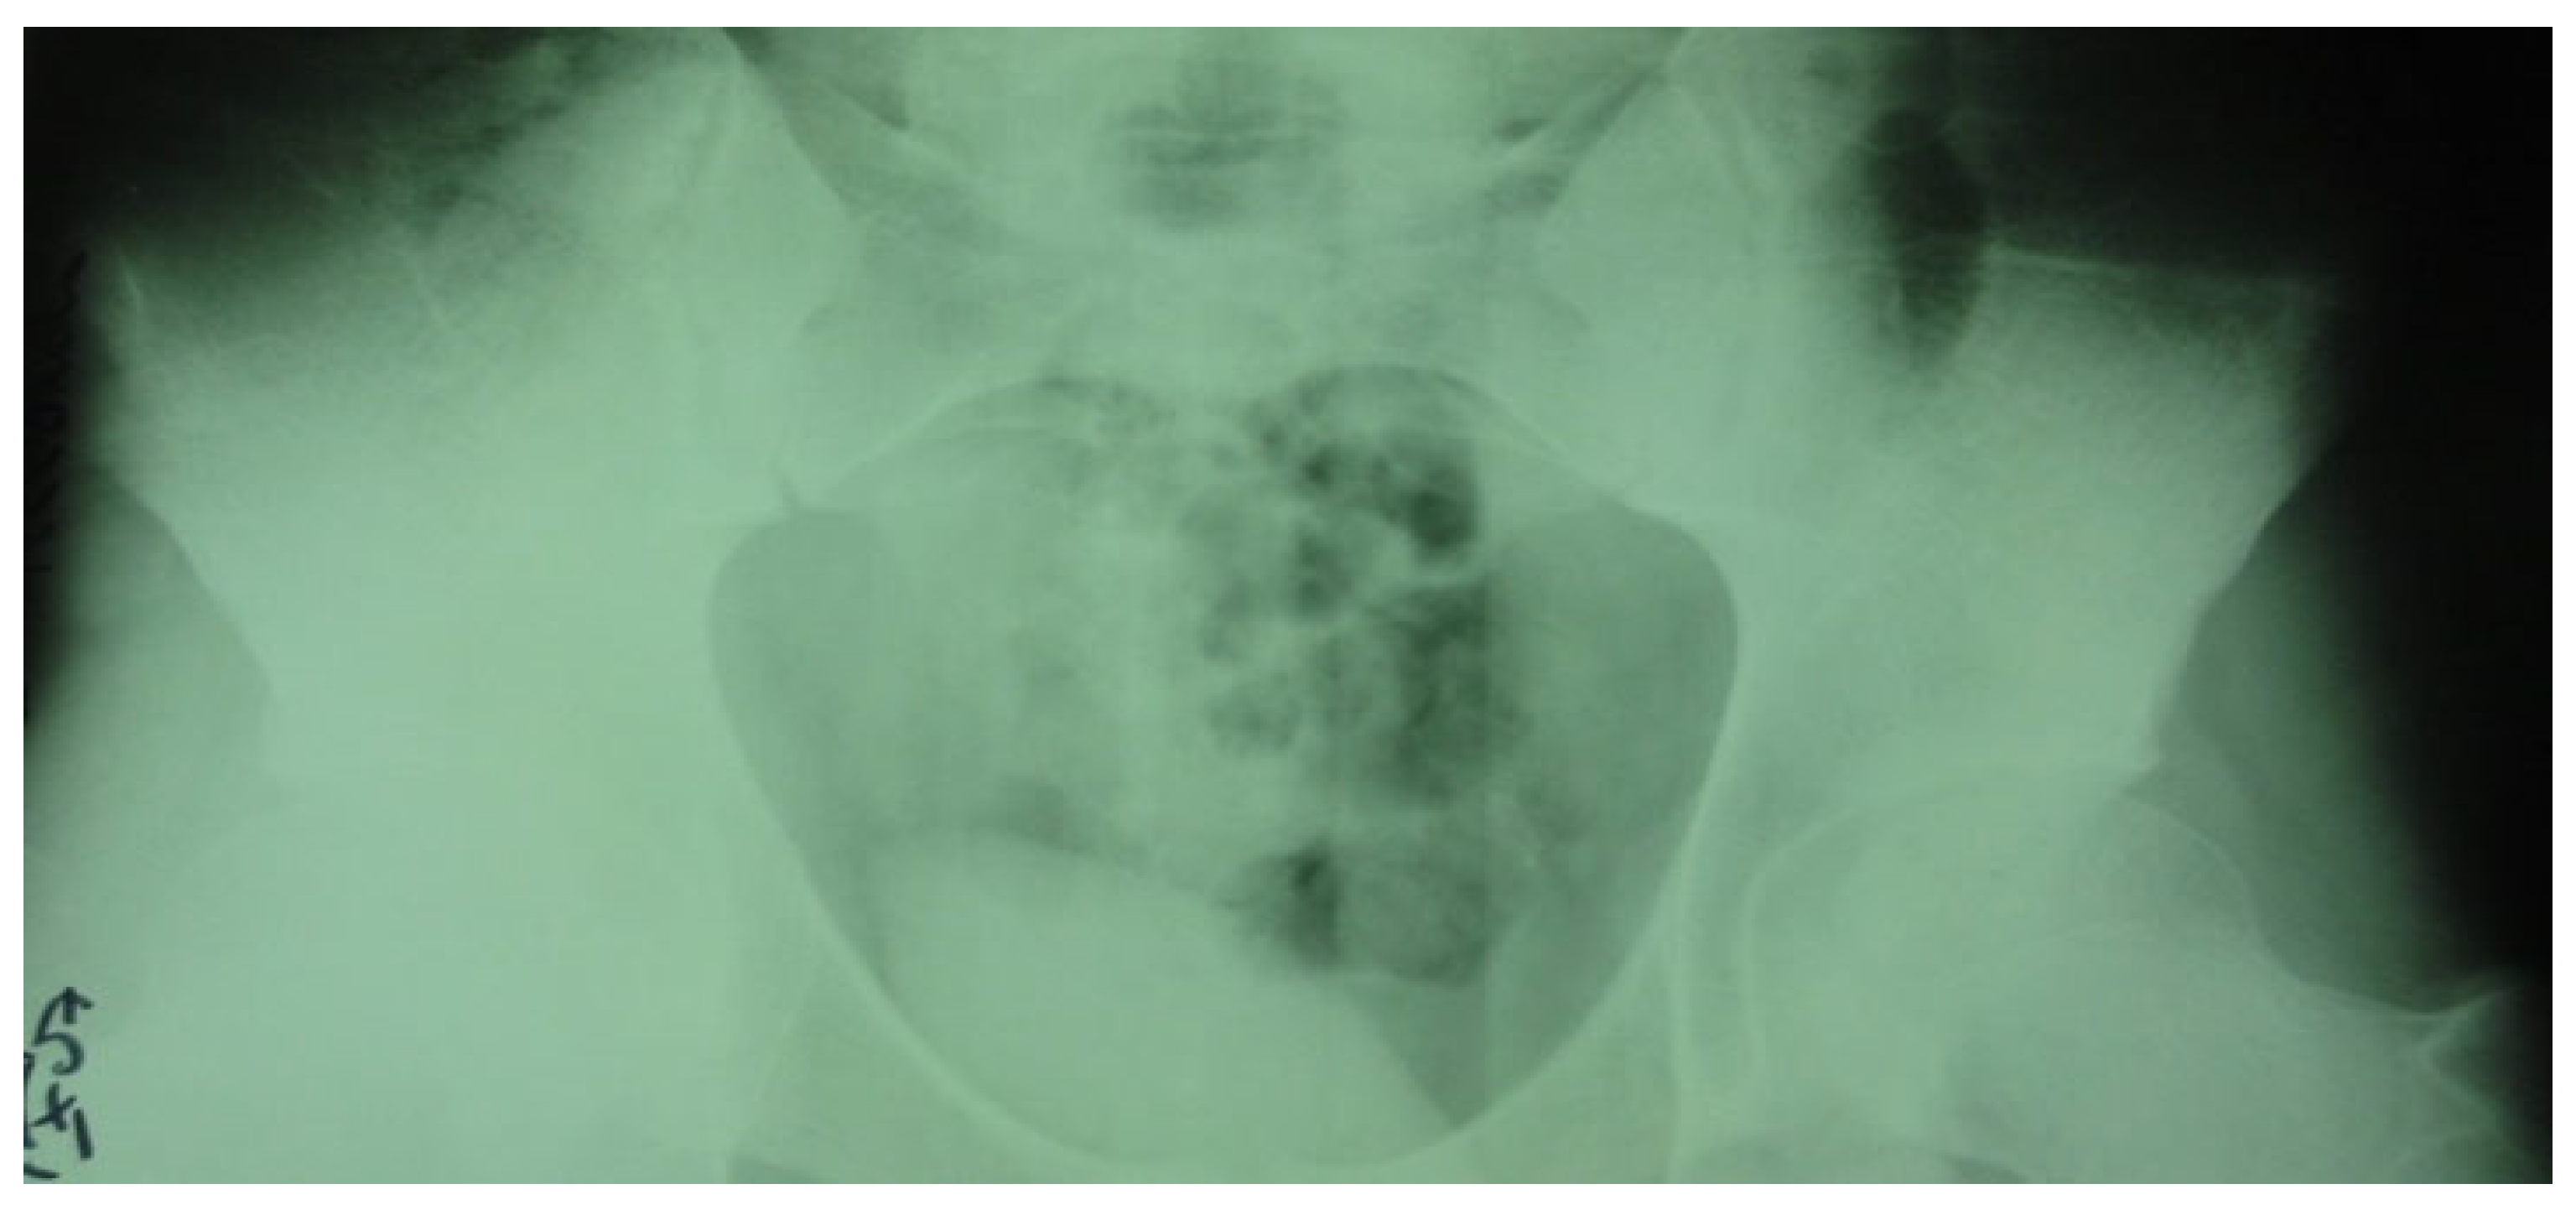

3.4. Case 4: Type III Accessory Navicular Impingement

A 26-year-old goalkeeper with a navicular injury, boasting six years of experience as a first-league professional in Romania, hails from an urban area and stands at 192 cm, weighing 95 kg. The latest case involves this goalkeeper, who, after sustaining a direct contact trauma during a match, reports experiencing pain and swelling in the dorsal part of his right forefoot. Forefoot X-ray diagnoses an improperly healed old right navicular fracture. As there was no trauma of the right foot, an MRI was performed, confirming the diagnosis of type III accessory navicular bone with impingement on the posterior tibial tendon.

In the second case, the patient, a left back, experienced pain in the inguinal region and left thigh while running during a national team training session. This 23-year-old national team member has six years of experience as a first-league professional in Romania, standing 202 cm tall and weighing 105 kg. Pelvic radiography was incorrectly performed (incorrectly) and the patient was diagnosed with left thigh muscle damage. (Figure 4).

Figure 4.

Incorrect pelvic X-ray.